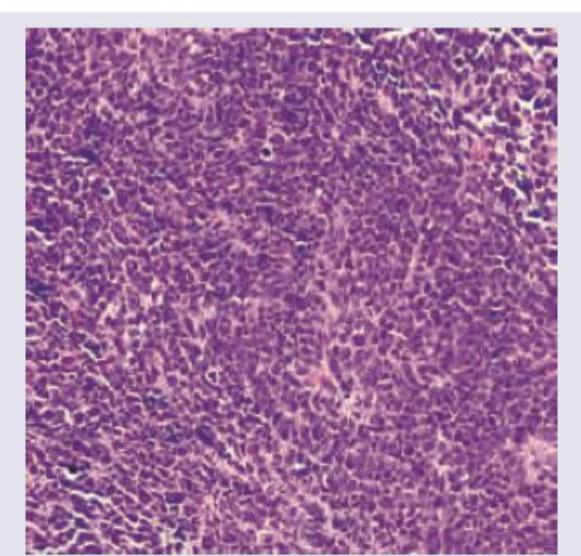

All are true about the type of lung cancer shown in the figure except: (Recent NEET Pattern 2016-17)

Explanation: ***Dense core granules are absent*** - This statement is incorrect because **small cell lung carcinoma (SCLC)**, characterized by diffuse sheets of hyperchromatic cells and positive synaptophysin, is a neuroendocrine tumor. - Neuroendocrine tumors, by definition, contain **dense core granules** which store neurosecretory products. Their absence would contradict the neuroendocrine nature of SCLC. *Diffuse sheets of hyperchromatic cells* - This is a characteristic histological feature of **small cell lung carcinoma (SCLC)**, where cells are small, round to oval, with scant cytoplasm and hyperchromatic nuclei, often forming diffuse sheets [1]. - The cells show **nuclear molding** and a high mitotic rate, consistent with aggressive growth. *Positive for Synaptophysin* - **Synaptophysin** is a neuroendocrine marker, and its positivity is a key immunohistochemical feature of **small cell lung carcinoma (SCLC)**, confirming its neuroendocrine differentiation [1]. - Other neuroendocrine markers like **chromogranin A** and **CD56** are also typically positive in SCLC. *3p allele loss* - Loss of heterozygosity on the **short arm of chromosome 3 (3p)** is a very common genetic alteration found in **small cell lung carcinoma (SCLC)** [2,4]. - This region harbors several **tumor suppressor genes**, including *FHIT* and *RASSF1A*, whose inactivation contributes to SCLC pathogenesis. **References:** [1] Cross SS. Underwood's Pathology: A Clinical Approach. 6th ed. Common Clinical Problems From Respiratory Tract Disease, pp. 337-338. [2] Kumar V, Abbas AK, et al.. Robbins and Cotran Pathologic Basis of Disease. 9th ed. The Lung, pp. 720-721. [3] Kumar V, Abbas AK, et al.. Robbins and Cotran Pathologic Basis of Disease. 9th ed. The Lung, p. 721.